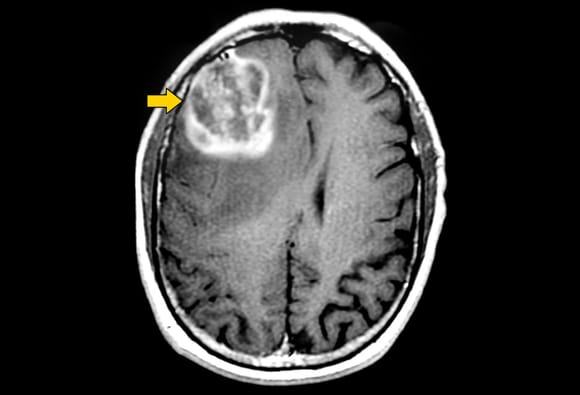

Brain Cancer Symptoms In Babies - Child Cancer Symptoms Be Child Cancer Aware / However, age, family history, and radiation treatments (to cure your cancer) are what put you at the highest risk of developing a cancerous tumor in your.. The most common symptoms of brain cancer can be listed. Cancer in children is the most stressful fear for any parents. Metastatic brain cancer is cancer that originated from another place, but has invaded the brain. Regardless of the position of a tumour, it has the. While these symptoms don't always indicate brain cancer, and in many cases are caused by less serious conditions, it's important to seek prompt.

Symptoms seen in this disease occur when the tumor presses the nerve endings, damages the brain, or grows and causes fluid to accumulate in the skull. These tissues include the cells that make up the membranes, blood difficulty walking and clumsiness are some of the more common symptoms that occur in a brain cancer patient because several parts of the brain. Brain cancer may develop gradually, without any noticeable signs or with minimal symptoms, and it may suddenly cause severe, rapidly worsening effects. This guide gives you all the more details about the brain cancer symptoms and causes. Brain cancers account for about 15% of pediatric cancers and are the second most common type of cancer in children. This is the insidiousness of cancerous tumors, because most situations with early detection of brain oncology occur by pure chance, when the patient does not even guess. That's a really scary term. For example, vision problems may result from a tumor near the optic nerve. The most common symptoms of brain cancer can be listed. Your doctor may not even find some (like tumors of the pituitary gland) unless they do an imaging test like ct scan or mri for another reason. Find out how the right treatment plan can fight cancerous brain. Although cancer is rare in children, brain and spinal cord tumors are the second most common type of childhood cancer, after leukemia. Developing cancer in other parts of the body can increase your chances of developing secondary cancer in the brain.

The symptoms of cancerous presence in your brain can trigger several symptoms. Memorial sloan kettering cancer center's pediatric brain tumor team diagnose and treat children, adolescents, and young adults who have any form of brain tumor. Symptoms seen in this disease occur when the tumor presses the nerve endings, damages the brain, or grows and causes fluid to accumulate in the skull. Since the brain controls learning the symptoms depend on the location and size of the tumor. In addition to these signs and symptoms of brain and spinal cord tumors, some children are unable to reach certain growth and development milestones such as sitting.